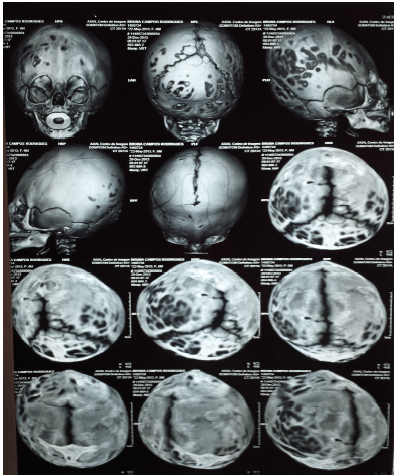

Criança de 9 meses, prematura de 30 semanas de idade gestacional, encaminhada para avaliação neurológica devido a um atraso do desenvolvimento neuropsicomotor leve. Foi solicitada uma tomografia de crânio que se vê abaixo.

A abordagem da doença detectada ao exame consiste em: